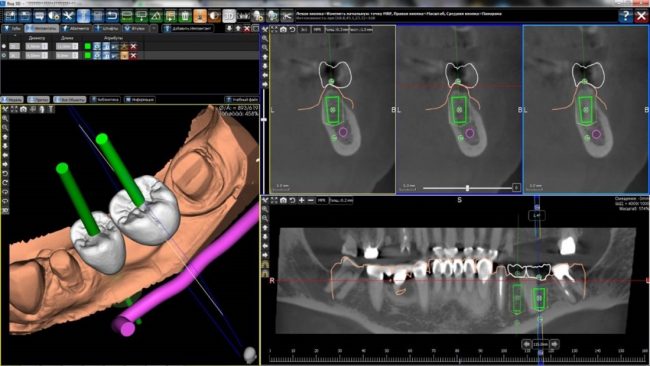

С «идеальными» (или близкими к идеальным) условиями всё вроде, как понятно. Сделали компьютерную томографию. Измерили существующие объемы костной ткани:

«Распечатанные» шаблоны, как правило, изготавливаются на основе совмещения 3D-модели зубного ряда с данными компьютерной томографии. В результате получаются достаточно точные направляющие, привязанные к существующему рельефу альвеолярного гребня (т. н. «накостный шаблон»):

Их удобно использовать в случаях, когда, стремясь избежать остеопластики, мы ставим имплантаты в заведомо экстремальное положение. Например, при протезировании по схеме All-On-4:

Либо в случаях, когда необходимо очень-очень точное позиционирование, в т. ч. по глубине. Вот тогда лучше накостных 3Д-шаблонов ничего нет.